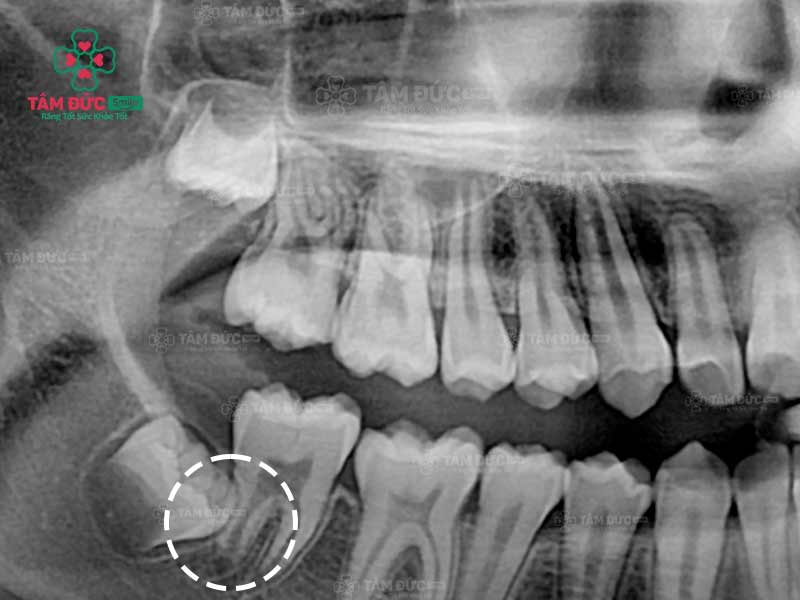

Quý khách có thể nhận biết răng khôn mọc ngầm thông qua phim chụp X-Quang

2. Cách nhận biết răng khôn đang mọc ngầm

Các triệu chứng của răng khôn mọc ngầm không rõ ràng nên Quý khách dễ nhầm lẫn với các cơn đau răng thông thường khác. Vì vậy, Quý khách nên đến nha khoa Tâm Đức Smile để các bác sĩ chụp X-Quang và xác định chính xác răng khôn đang mọc ngầm.

Trước khi nhổ bỏ răng khôn mọc ngầm, Quý khách được bác sĩ chụp X-quang răng và thực hiện các xét nghiệm máu cần thiết. Qua phim X-Quang, bác sĩ biết được ảnh hưởng của răng đang mọc ngầm để cân nhắc phương pháp điều trị thích hợp nhất.